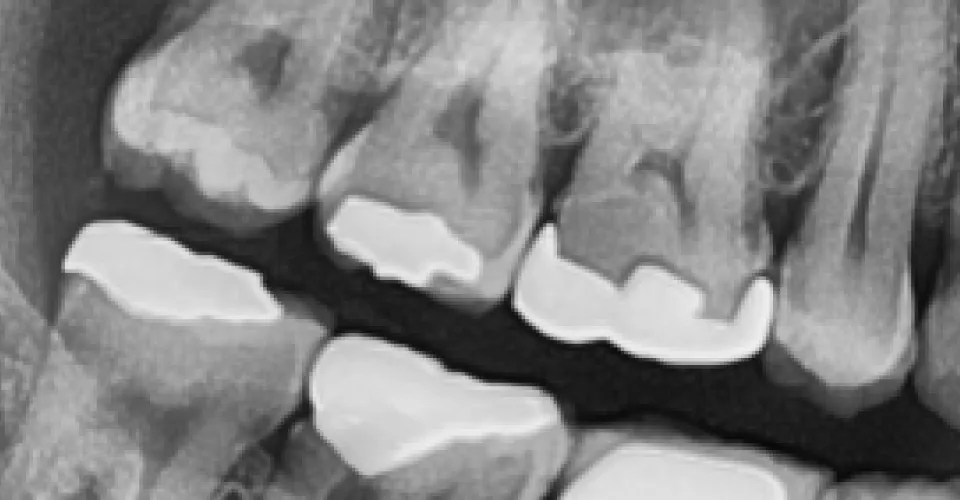

根管治療(歯の神経の治療)は、歯科治療の中で最も繊細かつ高度な技術を要する分野の一つです。 歯の内部にある「根管」は直径1mm以下と非常に狭く、かつ複雑に湾曲した迷宮のような構造をしています。この微細な空間から、汚染された神経や細菌を肉眼だけで完全に取り除くことは、例えるなら「暗闇の中で、手探りで針の穴を探す」ようなもの。 従来の「勘」や「経験」だけに頼る治療では、どうしても感染源の取り残しが生じやすく、それが再発や抜歯の原因となっていました。

だからこそ、LOTUS DENTAL CLINIC 東京(ロータスデンタルクリニック東京)では、歯の解剖学的構造を熟知した高度専門医が、歯科用CTによる科学的根拠(エビデンス)に基づいた診断を行い、マイクロスコープ下で確実な処置を行うこと。 「見えないもの」を「見える」状態にすることこそが、難症例であっても歯を救い、長期的な健康を守るための絶対条件であると私たちは考えています。

多くの保険診療では、唾液の侵入を防ぐ「ラバーダム防湿」が行われず、細菌感染のリスクに晒された状態で治療が進みます。また、肉眼や手探りの治療では、複雑に入り組んだ根の先端にある汚れを完全に取り除くことは困難です。

従来の2次元レントゲンでは、重なり合った根の形や、裏側に隠れた病巣の広がりを正確に把握することはできませんでした。

「診断」の精度が、歯の寿命を決定づけます。根管治療の成否は、実際に手を動かす前の「診査・診断」で9割が決まると言っても過言ではありません。 当院では、初診ですぐに削るようなことはいたしません。まずは患者様のお話を丁寧に伺い、歯科用CT(三次元断層撮影)を用いて、従来のレントゲンでは見えない複雑な根管形態や病巣の広がりを立体的に把握します。さらに、マイクロスコープ(歯科用顕微鏡)で歯の微細な亀裂(マイクロクラック)まで確認し、無駄な治療を回避するとともに、最短ルートでの治癒を目指す治療計画を東京都の極限まで歯を残す精密根管治療を行う当院では立案しています。